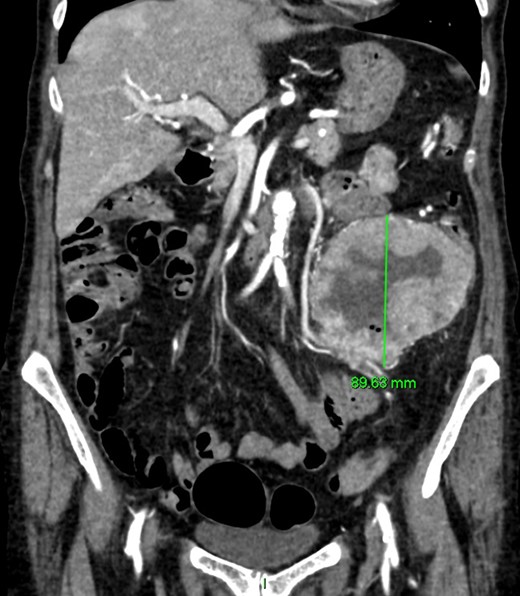

CT angiography (Figs 1 and 2)—large 9 cm exophytic cavitating lesion arising from jejunum with no evidence of active haemorrhage, with multiple further lesions in the duodenum. This was felt to be the source of the bleeding. Although the tumour was identified in this case by CT angiography, a simple contrast enhanced CT would almost certainly have demonstrated this tumour adequately, given the typical CT appearance of GIST, with significant contrast enhancement and heterogeneity.

Coronal CT imaging. Large exophytic cavitating lesion arising from jejunum with no evidence of active haemorrhage.